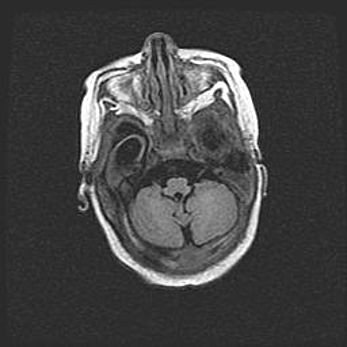

Подострая гематома правой гемисферы мозжечка.

Наружная гидроцефалия.

Возраст: 15 дней

Вес: 3100 г

Пол: женский

Окружность головы: 37 см

Срок гестации: 35-36 недель

При открытой наружной форме гидроцефалии у новорожденных расширяются и переполняются субарахноидные пространства.

Кровоизлияния в мозжечок имеют две клинико-анатомические формы: полушарные гематомы и кровоизлияния в червь.

К появлению этой патологии может привести: повреждения головного мозга, возникающие в результате асфиксии и гипоксии плода при беременности, или травмы во время родов. Редко гематома мозжечка может быть результатом первичной коагулопатии и сосудистой мальформации, диссеминированном внутрисосудистом свертывании, изоиммунной тромбоцитопении.